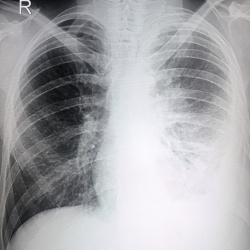

Добрый день. Подскажите пожалуйста, в верхних отделах правого легкого линейная тень. что это может быть : фиброзные изменения или дисковидный ателектаз. ? Спасибо